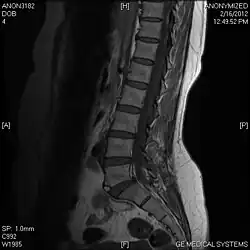

T1 W Sagittal

Limbus Vertebra L5